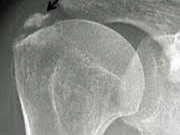

🔸 석회화 건염

힘줄 부위에 석회가 쌓이면서 심한 통증을 유발합니다. 급성으로 통증이 오고, 밤에 더 심해지는 경우가 많습니다.